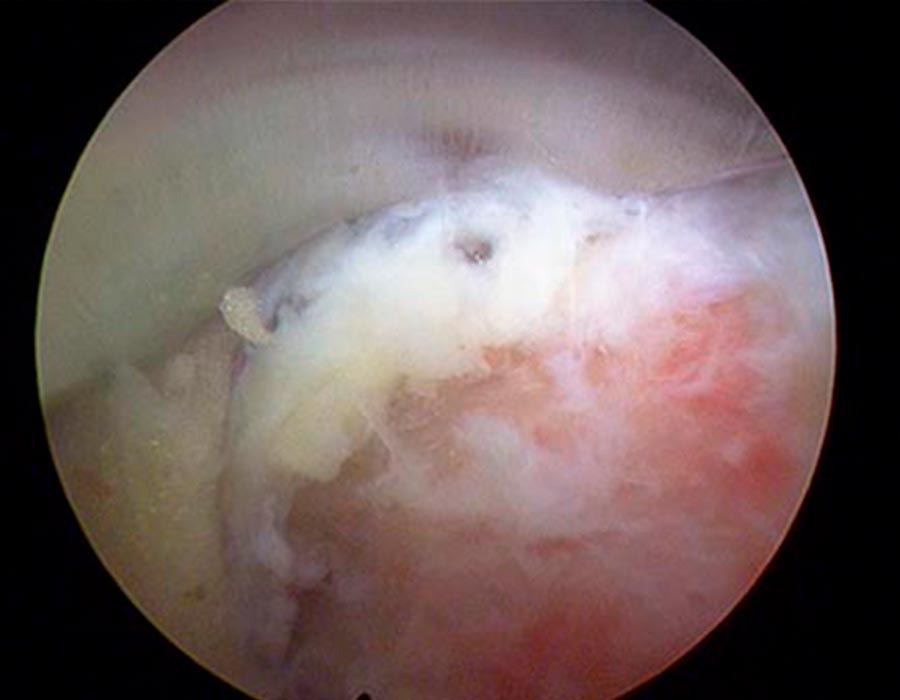

Para poder dar un diagnóstico observamos durante 6 meses la evolución de la paciente en el marco, y sobre la hernia foraminal L5-S1 y localizamos el problema. Presentaba una estenosis de canal entre las vértebras L4-L5 tal y como se puede ver en las siguientes imágenes.

Liberacion de estenosis de canal

Procedemos a la liberar de la estenosis el canal con mucha delicadeza y revisando que no quede ningún resto, todo ello mediante una incisión cutánea de 3mm muy precisa.

Tras realizar este vaciado comprobamos cómo queda adecuadamente liberadas las estructuras neurológicas vigilando que el espacio que queda ahora sea el correcto.